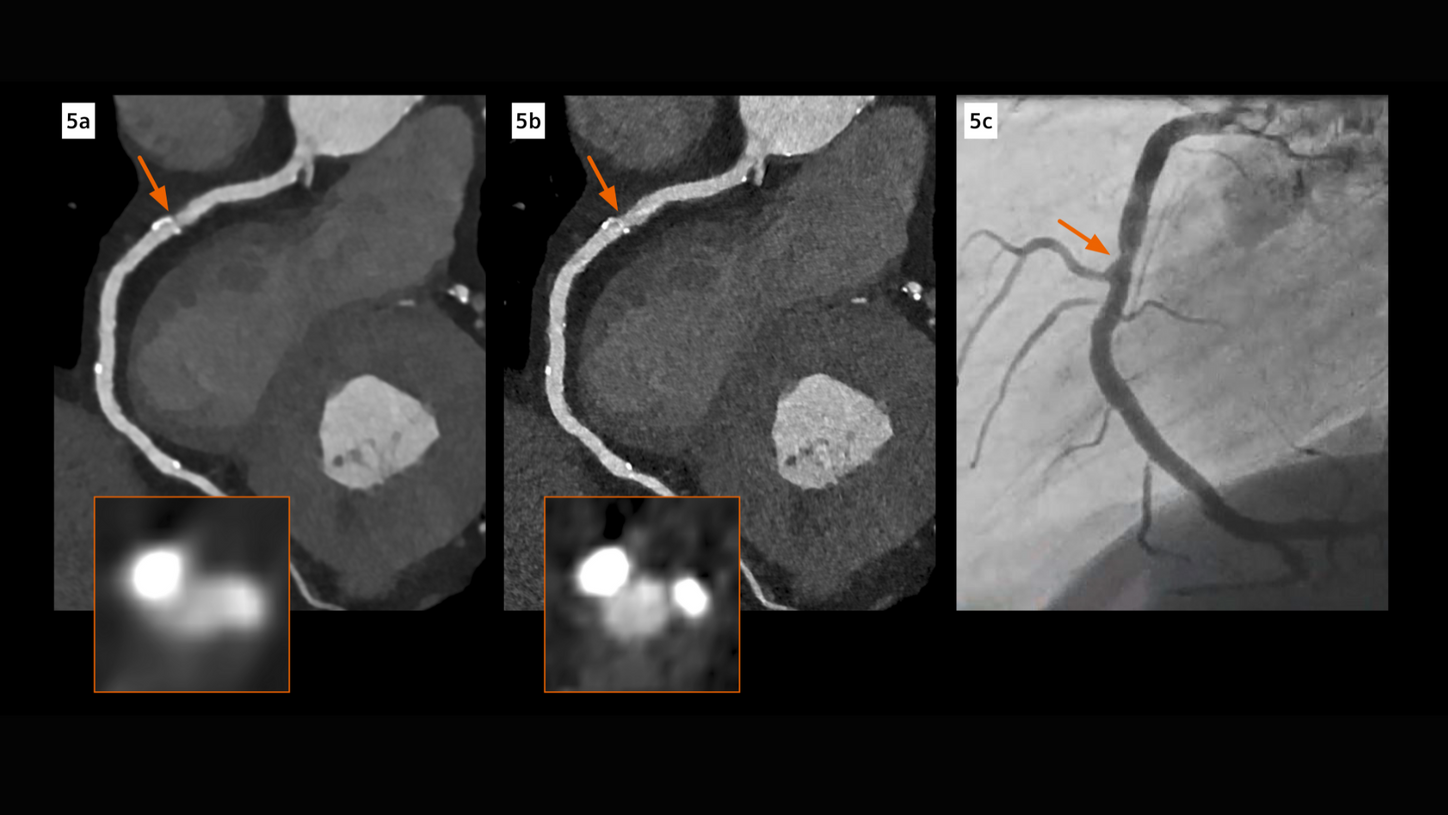

Courtesy of Center Cardio-Thoracique de Monaco, Monaco

NAEOTOM Alpha

Quantum PURE Lumen reconstruction of LAD.3